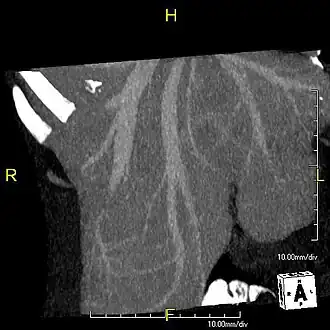

With the recent advances of noninvasive imaging, living liver donors usually have to undergo imaging examinations for liver anatomy to decide if the anatomy is feasible for donation. The evaluation is usually performed by multidetector row computed tomography (MDCT) and magnetic resonance imaging (MRI). MDCT is good in vascular anatomy and volumetry. MRI is used for biliary tree anatomy. Donors with very unusual vascular anatomy, which makes them unsuitable for donation, could be screened out to avoid unnecessary operations.

MDCT image. Arterial anatomy contraindicated for liver donation -

Phase contrast CT image. Contrast is perfusing the right liver but not the left due to a left portal vein thrombus.